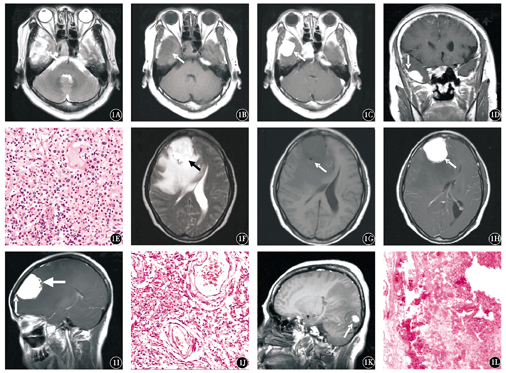

18例AM大部分呈类圆形,2例可见分叶;其中跨线生长3例,跨叶生长1例。17例病灶边界清晰,13例病灶周围可见水肿影,其中轻度水肿2例,中度水肿2例,重度水肿9例,1例可见出血影,所有病灶均未见钙化。T1WI呈等信号8例,等低信号3例,稍低信号4例,低信号2例,高低混杂信号1例;T2WI呈等高信号3例,稍高信号7例,等信号5例,高信号3例。增强扫描10例,明显均匀强化,其余8例为不均匀强化;5例病灶内可见坏死囊变区,14例(77.8 %)肿瘤组织内可见血管流空征,16例(88.9 %)病灶边缘与硬脑膜以宽基底相连,2例(11.1 %)以窄基底相连,15例(83.3 %)可见脑膜尾征,邻近骨质未见破坏,2例(11.1 %)可见脑积液。典型病例影像特征见图1。

1A~1E:例1,男性,44岁,晕倒后双上肢抽搐,口吐白沫,右侧颞部血管瘤型脑膜瘤;1A:MRI示横轴面T2WI示肿瘤呈类圆形无分叶(箭头所指),实性成分呈稍高信号,边界清晰,水肿较轻;1B:MRI示横轴位T1WI示肿瘤呈均匀等信号(箭头所指);1C:MRI示横轴面T1WI增强示肿瘤明显均匀强化(箭头所指);1D:冠状面T1WI增强示肿瘤以宽基底与大脑镰相连,可见脑膜尾征(箭头所指);1E:肿瘤细胞形态学检查示大量增生的血管,其间散在灶状合体细胞,胞质丰富,细胞界限不清,大小不等,核膜清楚,略呈空泡样;周围见薄层纤维组织 HE ×400;1F~1J:例2,女性,43岁,头痛、头晕、反应迟钝,右侧额部大脑镰旁血管瘤型脑膜瘤;1F:MRI示横轴面T2WI肿瘤呈浅分叶,边界清晰,水肿明显,邻近脑组织受压,呈稍高信号,后缘可见不规则更高信号(液化坏死)(箭头所指);1G:MRI示横轴面T1WI示肿瘤呈稍低信号,周围可见小圆形血管流空影(箭头所指);1H:MRI示横轴面T1WI增强示肿瘤明显强化,侧脑室明显受压(箭头所指);1I:MRI示矢状面T1WI增强示肿瘤强化欠均匀,内可见不规则低信号液化坏死区(粗箭头所指),与硬脑膜宽基底相连,可见脑膜尾征(细箭头所指);1J:肿瘤细胞形态学检查示丰富扩张的薄壁血管或血窦和分布其间的肿瘤细胞,肿瘤细胞胞质丰富,淡红染或透亮,细胞界限不清,大小不等,核膜清楚,细胞异型不明显,部分血管管壁增厚,玻璃样变,血管及血窦腔内可见大量红细胞 HE ×400;1K、1L:例3,女性,55岁,右侧头痛,右侧枕部血管瘤型脑膜瘤;1K:MRI示矢状面T1WI示肿瘤边界尚清,水肿明显,呈稍低信号,内可见斑状高信号(出血)(箭头所指);1L:细胞形态学检查示肿瘤组织由大小不等的血管构成,血管壁厚薄不均,血管间见漩涡状及合体状上皮样细胞 HE ×100

显微镜观察示,肿瘤组织由大量增生的厚壁、薄壁血管组成,大部分为毛细血管,部分血管直径大小不一,血管之间可见呈漩涡状及合体细胞样排列的脑膜瘤细胞。肿瘤细胞胞质丰富,淡红染或透亮,细胞界限不清,大小不等,核膜清楚,略呈空泡样(图1E),细胞异型性多不明显,无明显核分裂象,部分病灶肿瘤细胞异型性明显,可见1~4个核分裂象。部分血管管壁增厚,玻璃样变(图1J),多无明显坏死改变,部分病灶内可见出血和坏死灶(图1L),肿瘤组织周围可见薄层纤维组织包绕。7例患者行免疫组织化学检查:CD34+ 6例(其中2例为血管内皮部分表达),CD31+ 7例,EMA+ 6例,Vim+ 6例,S-100- 7例,GFAP- 6例,Ki-67阳性指数<1 % 5例,>5 % 1例,1例约为10 %。网状染色显示血窦样结构与毛细血管壁。